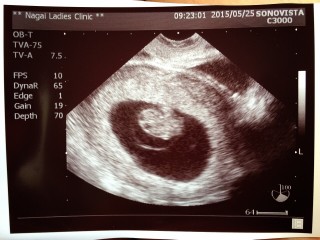

当初は一週遅れで育ってるって言われていたのですが、2週間後に見てみたら先生に「わ!でかい!」と言われました(笑)最終月経からの計算では8w3dでしたが、赤ちゃんを測ったら9w0d!手や体をバタバタ動かしている姿を主人と見て、感動しっぱなしでした^^あとは悪阻が過ぎ去るのを心待ちにしています(>_<)

8週目につわりがない日があったりして、不安になったりしたんですが9週目に育ってる姿を見て安心しました。 これは頭を下にして、横から見てるそうです。 二頭身で手も足もどこもかしこも可愛くて泣きそうになりました。へその緒もきれいに見えてちょっと感動しました。 どうかこのまま元気に育ってくれますように。。。